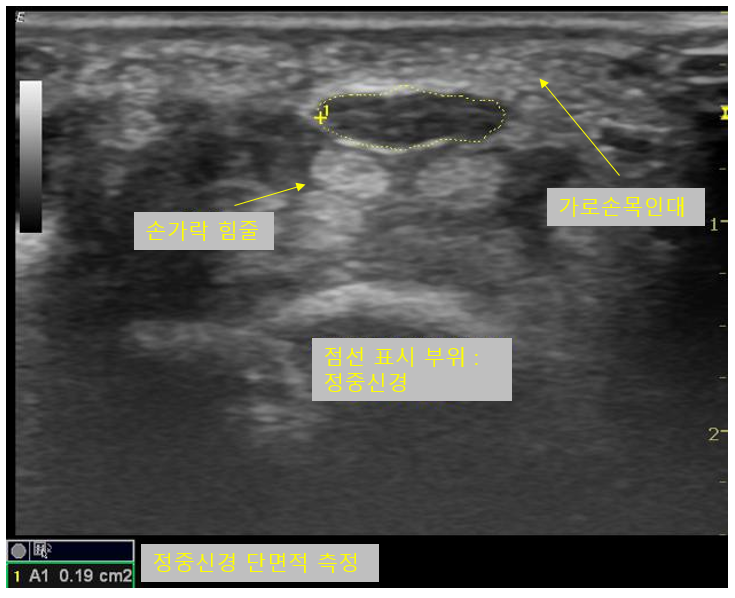

① 초음파 검사

초음파 검사에서 정중신경이 눌려있을 경우 초음파음영이 감소하여 정상보다 어둡게 보이며, 흔히 신경이 벌집모양으로 보인다고 설명하는데 벌집모양이 뚜렷하게 보이지 않고 소실될 수 있습니다. 좀더 객관적으로 데이터화 하기 위해 정중신경의 단면적을 측정할 수 있습니다. 신경이 눌릴 경우엔 눌린 부위보다 근위부에선 신경의 단면적이 증가하게 됩니다. 고무풍선과 같이 탄력성 있는 물체의 한쪽 부분을 눌렀을때를 생각해보시면 이해가 쉬우실것 같습니다.

한 부위에서만 단면적을 측정할 경우 정확성이 떨어질 수 있기 때문에 손목터널 보다 조금더 근위부에서도 측정하여 단면적의 차이가 기준치를 초과하는지 검사하기도 하고, 손목터널에서의 단면적과 전완부에서의 단면적의 비율로 판단하기도 합니다.